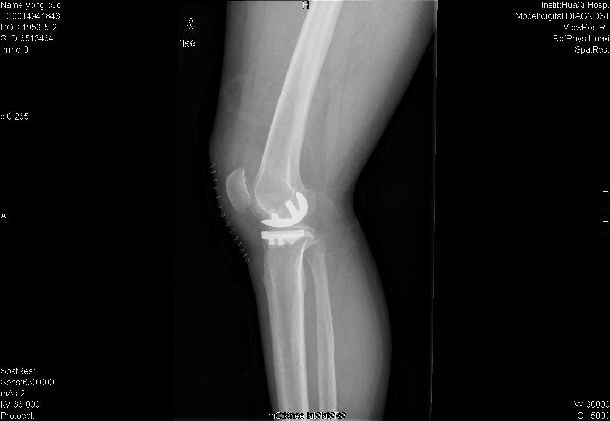

膝關(guān)節(jié)單髁置換術(shù)

膝關(guān)節(jié)單髁置換術(shù)針對(duì)的是膝關(guān)節(jié)單間室骨關(guān)節(jié)炎<病患,通過微創(chuàng)手術(shù)僅對(duì)膝關(guān)節(jié)病變的一側(cè)間室表面進(jìn)行置換,更換病變的軟骨面,保留全部的韌帶組織和其余間室關(guān)節(jié)軟骨,從而實(shí)現(xiàn)術(shù)后的快速康復(fù)。

(1)單髁置換術(shù)更微創(chuàng),術(shù)后療效優(yōu)異。常規(guī)全膝關(guān)節(jié)置換采用膝前正中切口,長度在13-375px,而單髁置換采用髕旁內(nèi)側(cè)弧形切口,長度僅200px。另外,由于保存了膝關(guān)節(jié)內(nèi)全部韌帶,術(shù)后患者膝關(guān)節(jié)活動(dòng)范圍更大,步態(tài)更接近正常,上下樓梯更加容易。